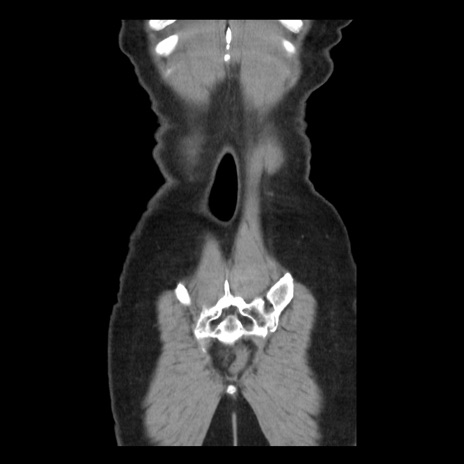

症例10(冠状断像)

【症例】 50歳代女性

【主訴】 腹痛

【現病歴】前日生レバーを食べた。今朝に排便あり。 昼前に突然発症の腹痛を生じ、当院救急外来を受診した。

【既往歴】 子宮筋腫にてで子宮全摘後

【身体所見】 意識清明、腹部:平坦、軟、下腹部やや左を中心に圧痛・反跳痛あり、筋性防御あり

【データ】WBC 7800、CRP 0.07